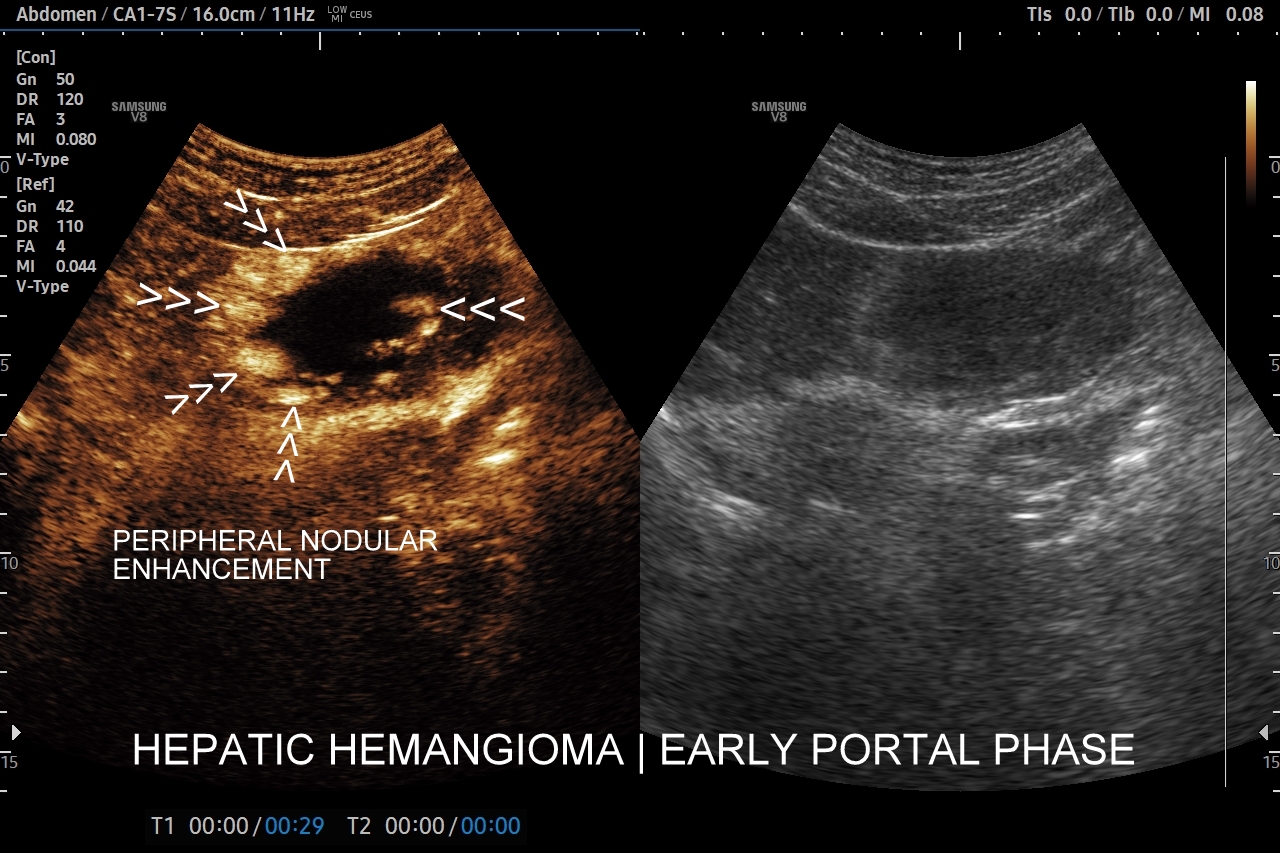

Najbardziej charakterystyczną cechą naczyniaka wątroby w badaniu CEUS jest jego wypełnianie w postaci guzkowej (ang. peripheral nodular enhancement) od obwodu ku centrum zmiany (ang. centripetal). Szybkość wypełniania bywa różnorodna, może być powolna lub szybka. W przypadku szybkiego wypełniania (tzw. flash-filling), w celu wykazania charakterystycznego centrypetalnego wypełniania niezbędna może być postprocessing’owa analiza poklatkowa zapisanego nagrania badania. W fazie późnej naczyniak wątroby pozostaje izowzmocniony lub hyperwzmocniony w stosunku do natywnego miąższu wątroby.

W przypadku dużych naczyniaków obszary, które uległy wykrzepianiu pozostają awaskularne przez wszystkie fazy badania CEUS, tj. nie wypełniają się kontrastem (nonenhancing). W przeciwieństwie do powyższego konstelacja, w której to w fazie wczesnej pojawia się wzmocnienie, a następnie w fazie wrotnej lub późnej ulega wypłukaniu (hypoenhancement) świadczy o cechach złośliwych diagnozowanej zmiany ogniskowej w wątrobie i wyklucza rozpoznanie naczyniaka.